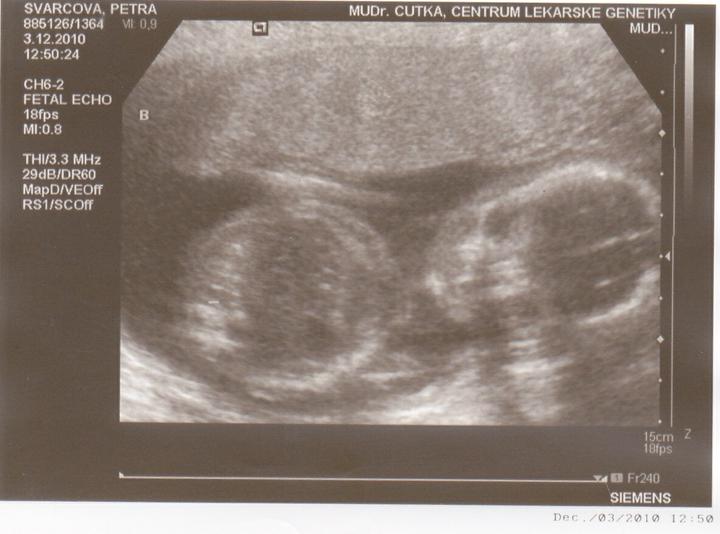

3.12-Jedu do Českých budějovic na ultrazvuk.Jsem zvědavá jak miminka povyrostly za ten měsíc co jsem tam byla naposled.Ale zároveń se bojím jestli jsou v pořádku.

Včera jsem Byla v Českých Budějovicíh.Jedno mimi váží 267g, a druhé váží 314g.A jsou to kluci.